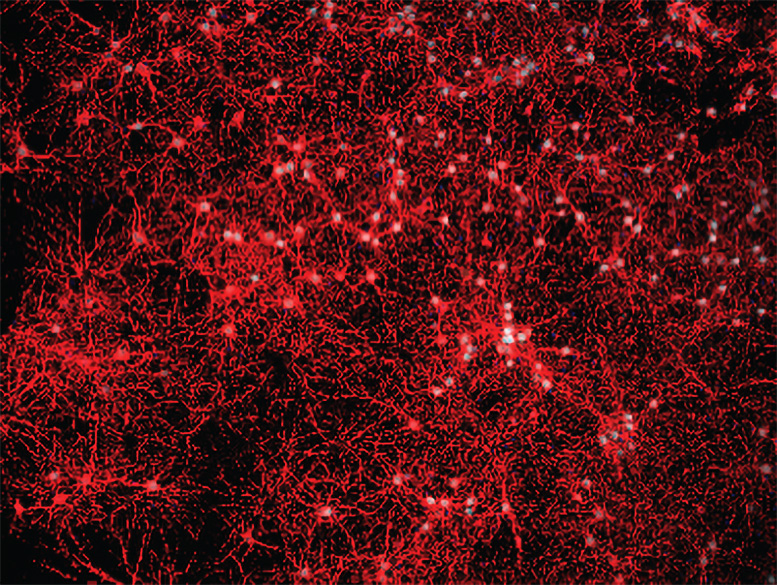

אימונופלואורסצנטי שימש לאימות טוהר תרבית תאים ראשונית. קרדיט: מעבדת צ'ון